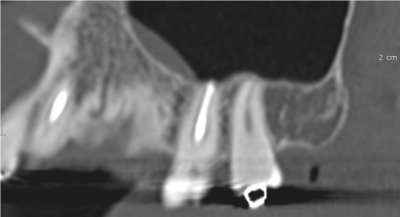

Le cone beam est une nouvelle technique de radiographie numérisée situé entre le panoramique dentaire et le scanner, il utilise un faisceau d’irradiation de forme conique d'où son nom. Cet appareil présente notamment l’avantage d’être plus précis que le panoramique dentaire et il possède une résolution similaire, voire supérieure à celle du scanner, avec en plus la possibilité d’une reconstruction numérique en 3D.

Il permet de balayer en un seul passage l’ensemble du volume à radiographier et en étant moins irradiant que le scanner.

Le cone beam utilisé en pathologie dentaire et maxillo-faciale est indiqué pour l’examen des tissus minéralisés (dents, cartilages, os), il permet d’identifier les lésions osseuses, les fractures, les infections, les kystes ou les corps étrangers.

Il est un examen de choix en implantologie.

Il évalue au plus juste le volume osseux et la position des structures anatomiques comme les nerfs en vue de la pose d’implants. La modélisation en 3D permet la taille et la forme des implants proportionnellement à la morphologie du patient et de simuler virtuellement leurs emplacements.